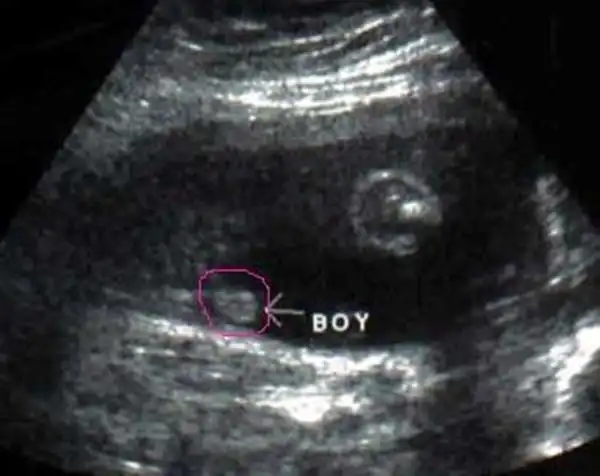

男胎儿小鸡四维显示图b超图看胎儿性别图解

男宝宝通过四维彩超图看清胎儿性别,在六个月以后照四维彩超,只要宝宝

四维彩超看到的胎儿生理结构图

男孩的小睾丸和女孩的小阴唇,在b超下看完全是两个不同的东东